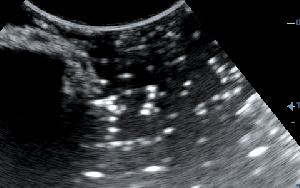

3) Τη συχνότητα, δηλαδή όσο πιο μεγάλη είναι αυτή, τόσο πιο πολλές λεπτομέρειες βλέπουμε αλλά ταυτόχρονα αυξάνονται τα τεχνουργήματα από αέρα και άλλες δομές. Οι αρμονικές βοηθούν στην καταστολή αυτών των τεχνουργημάτων.

Σημαντικό ρόλο επίσης παίζει η κλίση της βελόνας σε σχέση με τον ηχοβολέα ( κεφαλή ), όσο πιο κάθετη είναι η βελόνα με τον ηχοβολέα τόσο καλύτερη εικόνα της βελόνας έχουμε, όσο αυξάνεται η κλίση τόσο μειώνεται η διακριτική μας ικανότητα.

Λόγω της κλίσης βλέπουμε μόνο την μύτη της βελόνας.

Η βελόνα εμφανίζεται κάθετα προς τον ηχοβολέα.